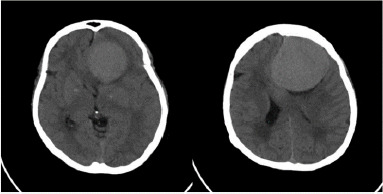

Case report: We present a case of a 59-year-old female with a history of progressive headache, anosmia, mental status changes, and progressive poor vision. Ocular examination revealed disc pallor in her left eye with disc oedema in the contralateral eye. The patient was sent for computerized tomography (CT) and MRI, and the diagnosis of frontal lobe meningioma was confirmed. The surgical removal was performed, and the condition improved gradually.